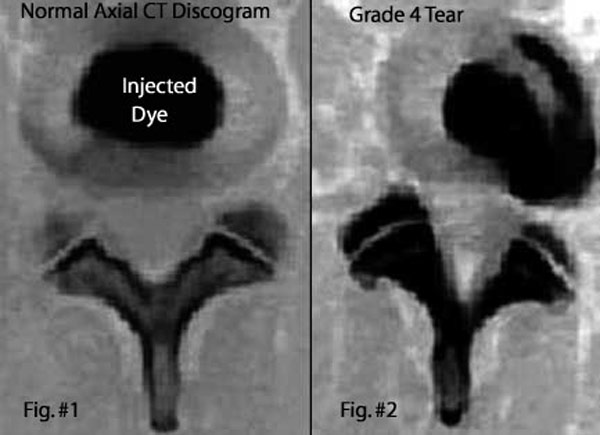

চোখের জলের ক্যাটালগ

অশ্রুবিন্দুর কেলাস। এই ভাবেই পাওয়া যাবে টিয়ার্স ব্যাঙ্কে।

তারও উপায় বের করেছেন সবেলই। বললেন, ‘‘যাতে চোখের জলের রাসায়নিক উপাদানগুলি দীর্ঘ সময় ধরে একেবারে ঠিকঠাক থাকে, সে জন্য আমরা তাকে ঠাণ্ডায় জমিয়ে রাখার উপায়ও উদ্ভাবন করেছি। তার কয়েকটি ধাপ রয়েছে। তরল নাইট্রোজেনকে ব্যবহার করতে হয়। যা চোখের জলের তাপমাত্রা শূন্যের ৮০ ডিগ্রি সেলসিয়াস নীচে নামিয়ে দেয়। মানে, মাইনাস ৮০ ডিগ্রি সেলসিয়াসে। ক্রায়োজেনিক পদ্ধতিতে সেই ঠাণ্ডায় জমানো চোখের জলকে রাখা হবে ব্যাঙ্কে। রক্ত, মূত্র, বিভিন্ন অ্যাম্নায়োটিক ফ্লুইডের মতো চোখের জলও কেনা বা পাওয়া যাবে অনলাইন অর্ডারের ভিত্তিতে। ওই ব্যাঙ্কে থাকবে বিভিন্ন বয়সের নারী ও পুরুষের চোখের জল। তার ফলে যে চোখের জল পেতে এখন গবেষক ও ওষুধ প্রস্তুতকারী সংস্থাগুলির কালঘাম ছুটে যায়, তা দু’সপ্তাহের মধ্যেই তাঁদের হাতে পৌঁছে যাবে। ‘সিলিকন ভ্যালি’রও খুব প্রয়োজন হবে চোখের জলের, সর্বাধুনিক প্রযুক্তির কনট্যাক্ট লেন্স বানাতে।’’